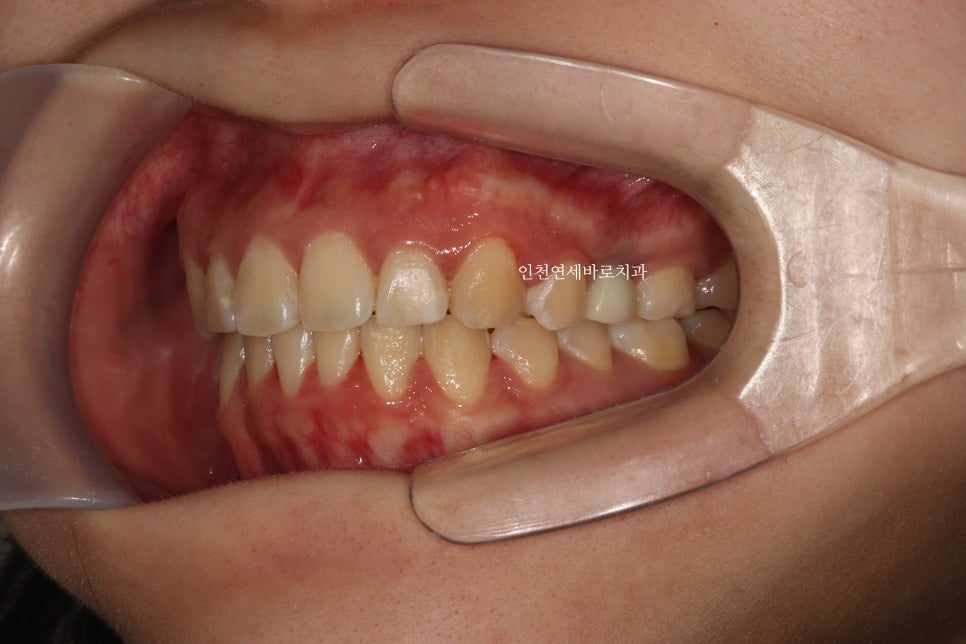

재제작했던 두번째 세트까지 모두 마무리 후

임플란트의 머리, 충치치료했던 치아의 크라운까지 모두 치료를 마무리 한 모습입니다.

재제작 전에 비해 정리된 교합을 확인할 수 있죠?